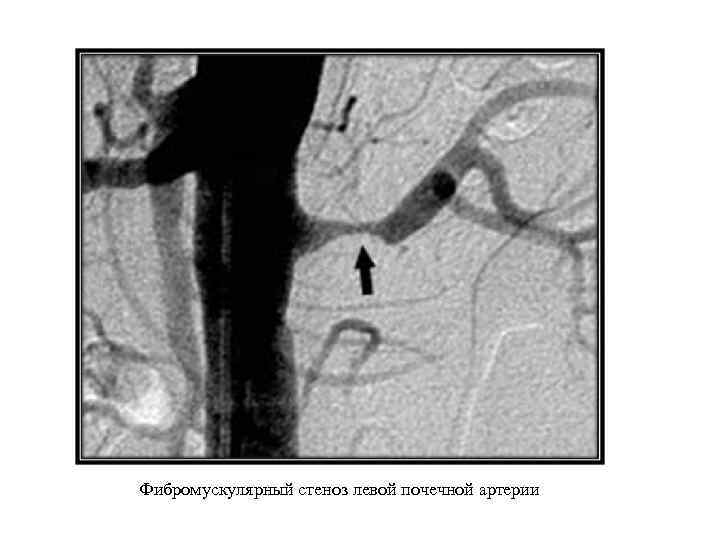

Аномалии почечных сосудов Аномалии количества: солитарная почечная артерия; сегментарные почечные артерии (двойная, множественные). Аномалии положения: поясничная; подвздошная; тазовая дистопия почечных артерий. Аномалии формы и структуры артериальных стволов: аневризмы почечных артерий (одно- и двусторонние); фибромускулярный стеноз почечных артерий; коленообразная почечная артерия. Врожденные артериовенозные фистулы. Врожденные изменения почечных вен: аномалии правой почечной вены (множественные вены, впадение вены яичка в почечную вену справа); аномалии левой почечной вены (кольцевидная левая почечная вена, ретроаортальная левая почечная вена, экстракавальное впадение левой почечной вены).

Аномалии почечных сосудов Аномалии количества: солитарная почечная артерия; сегментарные почечные артерии (двойная, множественные). Аномалии положения: поясничная; подвздошная; тазовая дистопия почечных артерий. Аномалии формы и структуры артериальных стволов: аневризмы почечных артерий (одно- и двусторонние); фибромускулярный стеноз почечных артерий; коленообразная почечная артерия. Врожденные артериовенозные фистулы. Врожденные изменения почечных вен: аномалии правой почечной вены (множественные вены, впадение вены яичка в почечную вену справа); аномалии левой почечной вены (кольцевидная левая почечная вена, ретроаортальная левая почечная вена, экстракавальное впадение левой почечной вены).

Множественные артериовенозные фистулы (стрелки)

Множественные артериовенозные фистулы (стрелки)